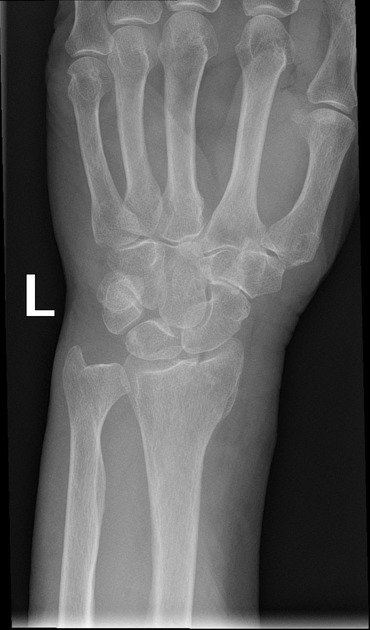

Colles Fracture

• Extra Articular fracture of distal radius with dorsal angulation (of the distal fracture fragment).

• Caused by FOOSH with extended wrist and pronated forearm.

Case courtesy of Frank Gaillard, Radiopaedia.org, rID: 12382 (Colles case)